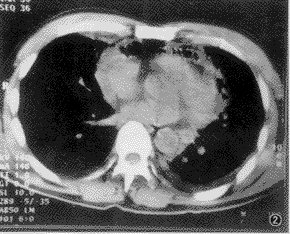

2.X線檢查

①臨床症狀與胸片所見不一致。當肺炎初起時,臨床症狀已很重,而X線徵象卻很少,僅表現為肺紋理重,一側或雙側出現小片浸潤影;當臨床症狀已趨明顯好轉時,在胸片上卻可見明顯病變如肺膿腫和肺大泡等現象。②病變發展迅速,甚至在數小時內,小片炎變就可發展成膿腫。③病程中,多合併小膿腫、膿氣胸、肺大泡。嚴重的還並發縱隔積氣、皮下氣腫及支氣管胸膜瘺。④胸片上病灶陰影持續時間較一般細菌性肺炎為長,在2個月左右陰影仍不能完全消失。

X線檢查: